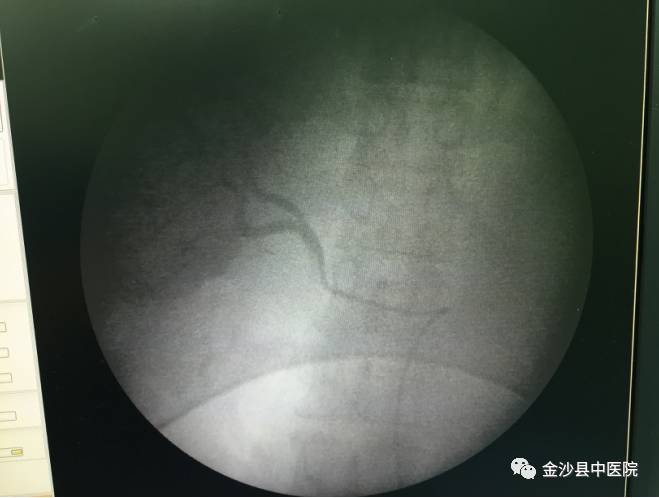

专家在进行经导管肝动脉化疗栓塞术

肝动脉化疗栓塞术